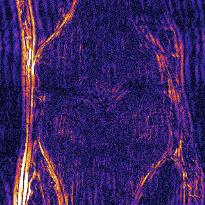

Recently, deep neural networks have greatly advanced undersampled Magnetic Resonance Image (MRI) reconstruction, wherein most studies follow the one-anatomy-one-network fashion, i.e., each expert network is trained and evaluated for a specific anatomy. Apart from inefficiency in training multiple independent models, such convention ignores the shared de-aliasing knowledge across various anatomies which can benefit each other. To explore the shared knowledge, one naive way is to combine all the data from various anatomies to train an all-round network. Unfortunately, despite the existence of the shared de-aliasing knowledge, we reveal that the exclusive knowledge across different anatomies can deteriorate specific reconstruction targets, yielding overall performance degradation. Observing this, in this study, we present a novel deep MRI reconstruction framework with both anatomy-shared and anatomy-specific parameterized learners, aiming to "seek common ground while reserving differences" across different anatomies.Particularly, the primary anatomy-shared learners are exposed to different anatomies to model flourishing shared knowledge, while the efficient anatomy-specific learners are trained with their target anatomy for exclusive knowledge. Four different implementations of anatomy-specific learners are presented and explored on the top of our framework in two MRI reconstruction networks. Comprehensive experiments on brain, knee and cardiac MRI datasets demonstrate that three of these learners are able to enhance reconstruction performance via multiple anatomy collaborative learning.